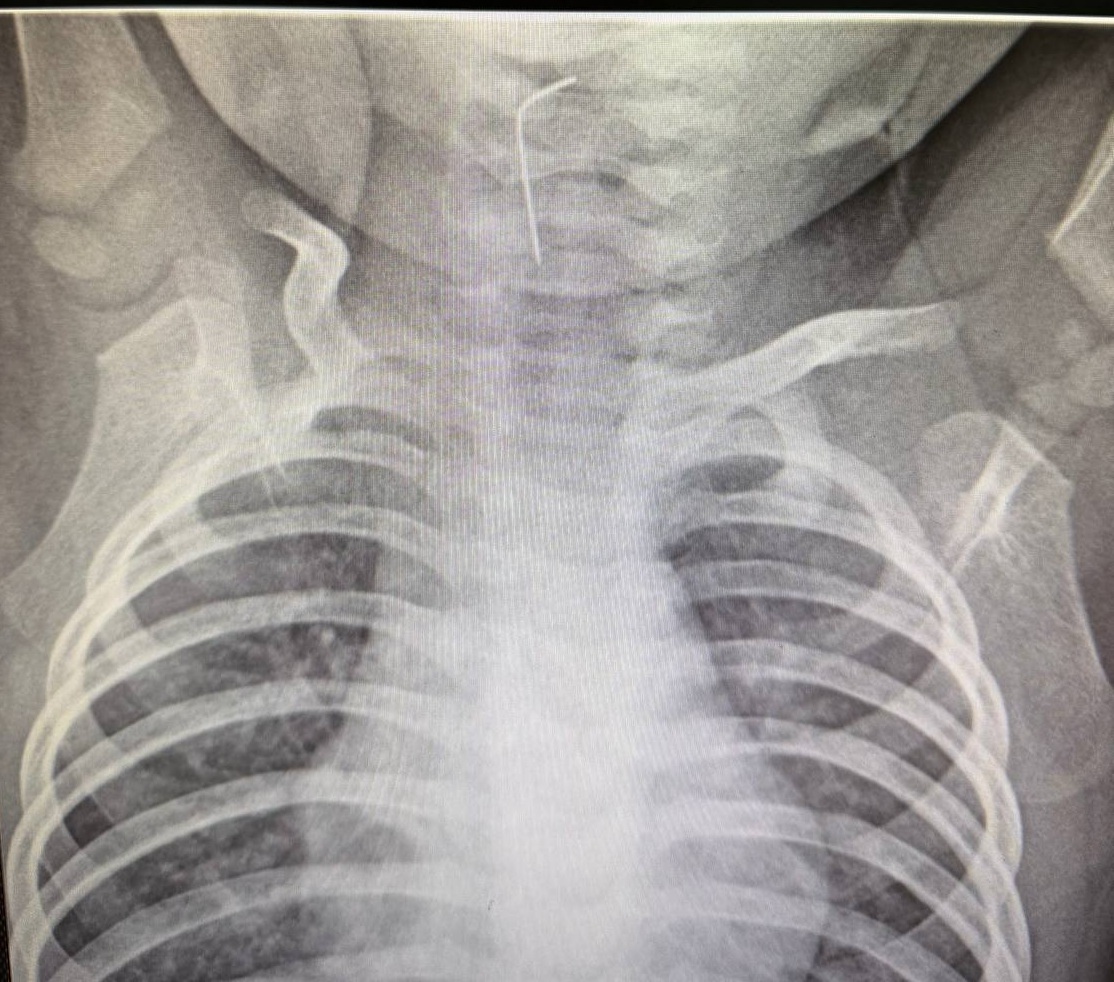

Как выяснилось, ребенок проглотил иглу. Специалисты больницы незамедлительно провели рентгенологическое исследование и применили эндоскопический метод. В результате было определено точное местоположение инородного тела, и иглу, застрявшую в пищеводе, успешно извлекли.

Фото: акимат Туркестанской области